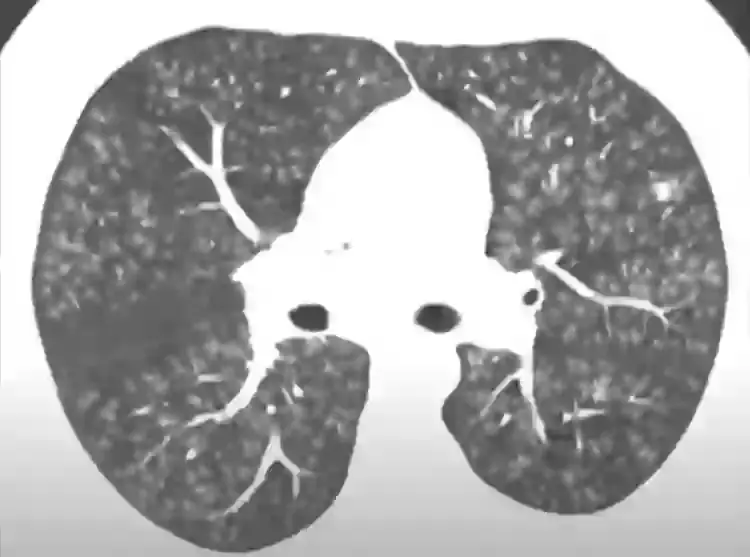

Popcorn lung, or bronchiolitis obliterans as it's actually called, is a rare chronic disease which occurs when airways in the lungs are scarred, leading to breathing difficulties, coughing, and wheezing.

The first cases of bronchiolitis obliterans were discovered in workers in a microwavable popcorn factory as people were breathing in diacetyl—the buttery-flavoured chemical which used to be found in things such as caramel, popcorn and dairy products. Which is obviously where the disease got its more commonly used name from.